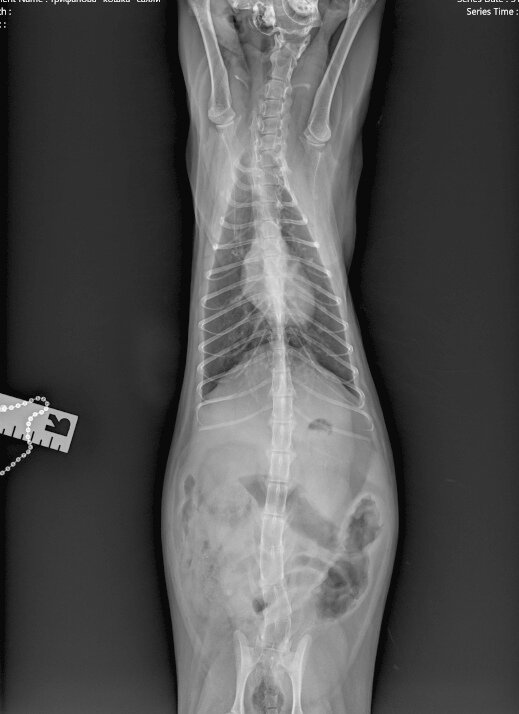

На сегодняшний день долг в клинике 800 за рентген кошки Салли с сердечной отдышкой. Врач назначил УЗИ СЕРДЦА, никак не может женщина сейчас себе его позволить. Кошечка Салли: очередной пример, когда ветеринары не дают пояснений волонтеру...

Салли